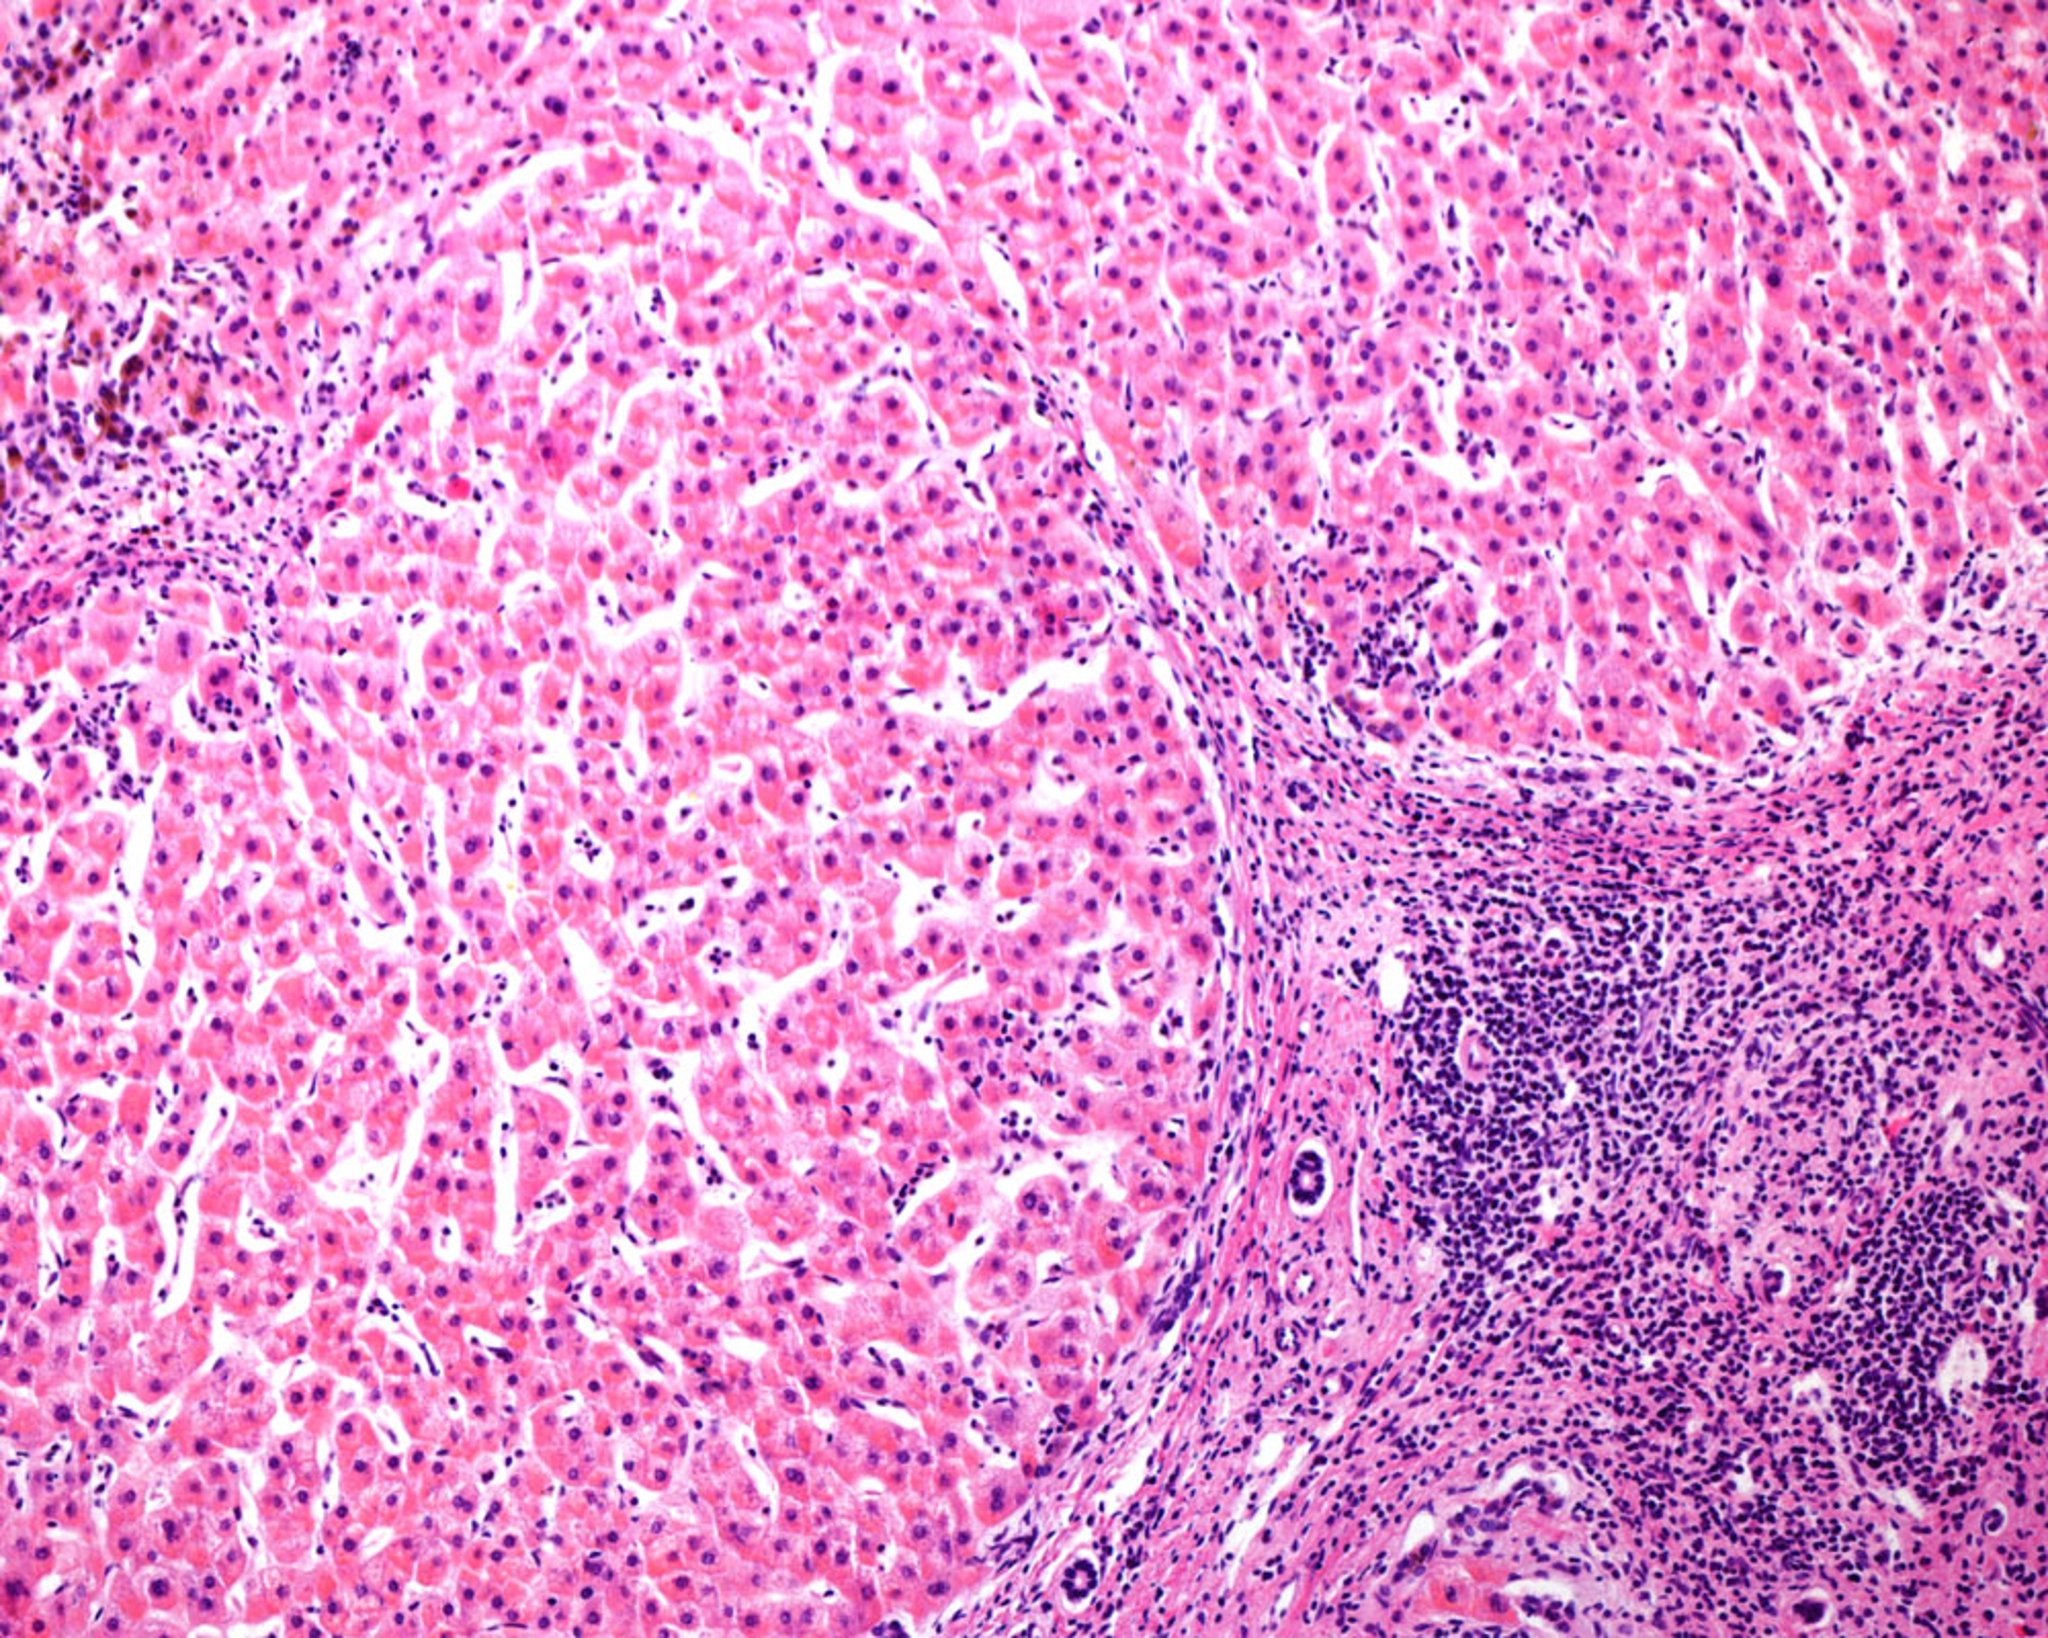

Cirrosi micronodulare nel fegato umano (micrografia ottica)

Micrografia ottica di un fegato umano con cirrosi micronodulare, una frequente conseguenza dell'epatite alcolica. I noduli rigeneranti sono separati da setti di tessuto connettivo che mostrano infiltrati infiammatori cronici. Si noti l'assenza di una vena centrale nei noduli e di triadi portali nei setti di tessuto connettivo.